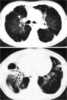

Usual interstitial pneumonia (UIP) is a form of lung disease characterized by progressive scarring of both lungs. The scarring (fibrosis) involves the supporting framework (interstitium) of the lung. [Source: Wikipedia ]